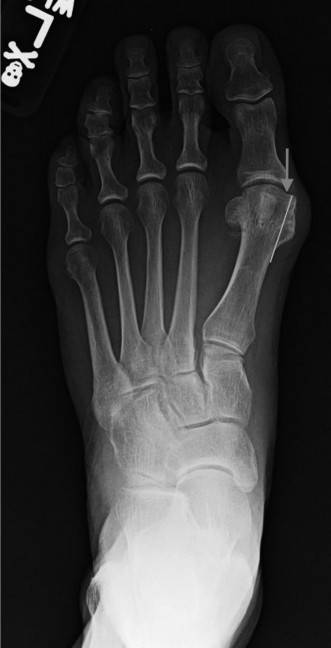

Shaft Osteotomies (e.g., Scarf, Ludloff): Used for moderate to severe deformities (IMA > 16-18°).

- These are more powerful corrections, allowing for greater translation, rotation, and plantarflexion/dorsiflexion adjustments.

- Fixation typically involves two screws.

Figure 5: Radiographic depiction of a stabilized osteotomy (e.g., Scarf), demonstrating the correction of the IM angle and use of internal fixation. -